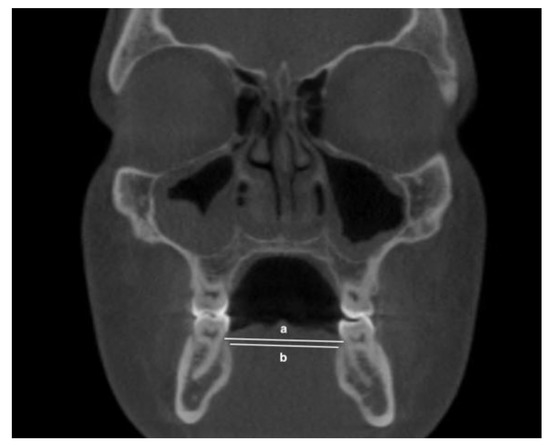

- Mandibular inter-lingual bone widths: from the right to the left points at the level of alveolar crest and furcation (Figure 4)